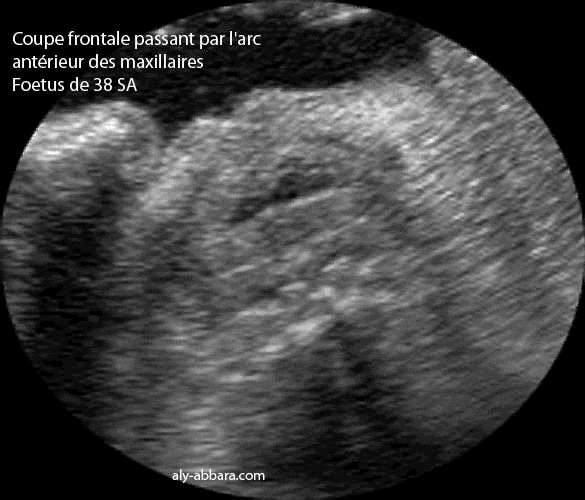

Coupe échographique frontale passant par l'arc antérieur du maxillaire inférieur et mettant en évidence les incisives inférieures encore enfuites dans la mandibule

fœtus âgé de 38 SA.